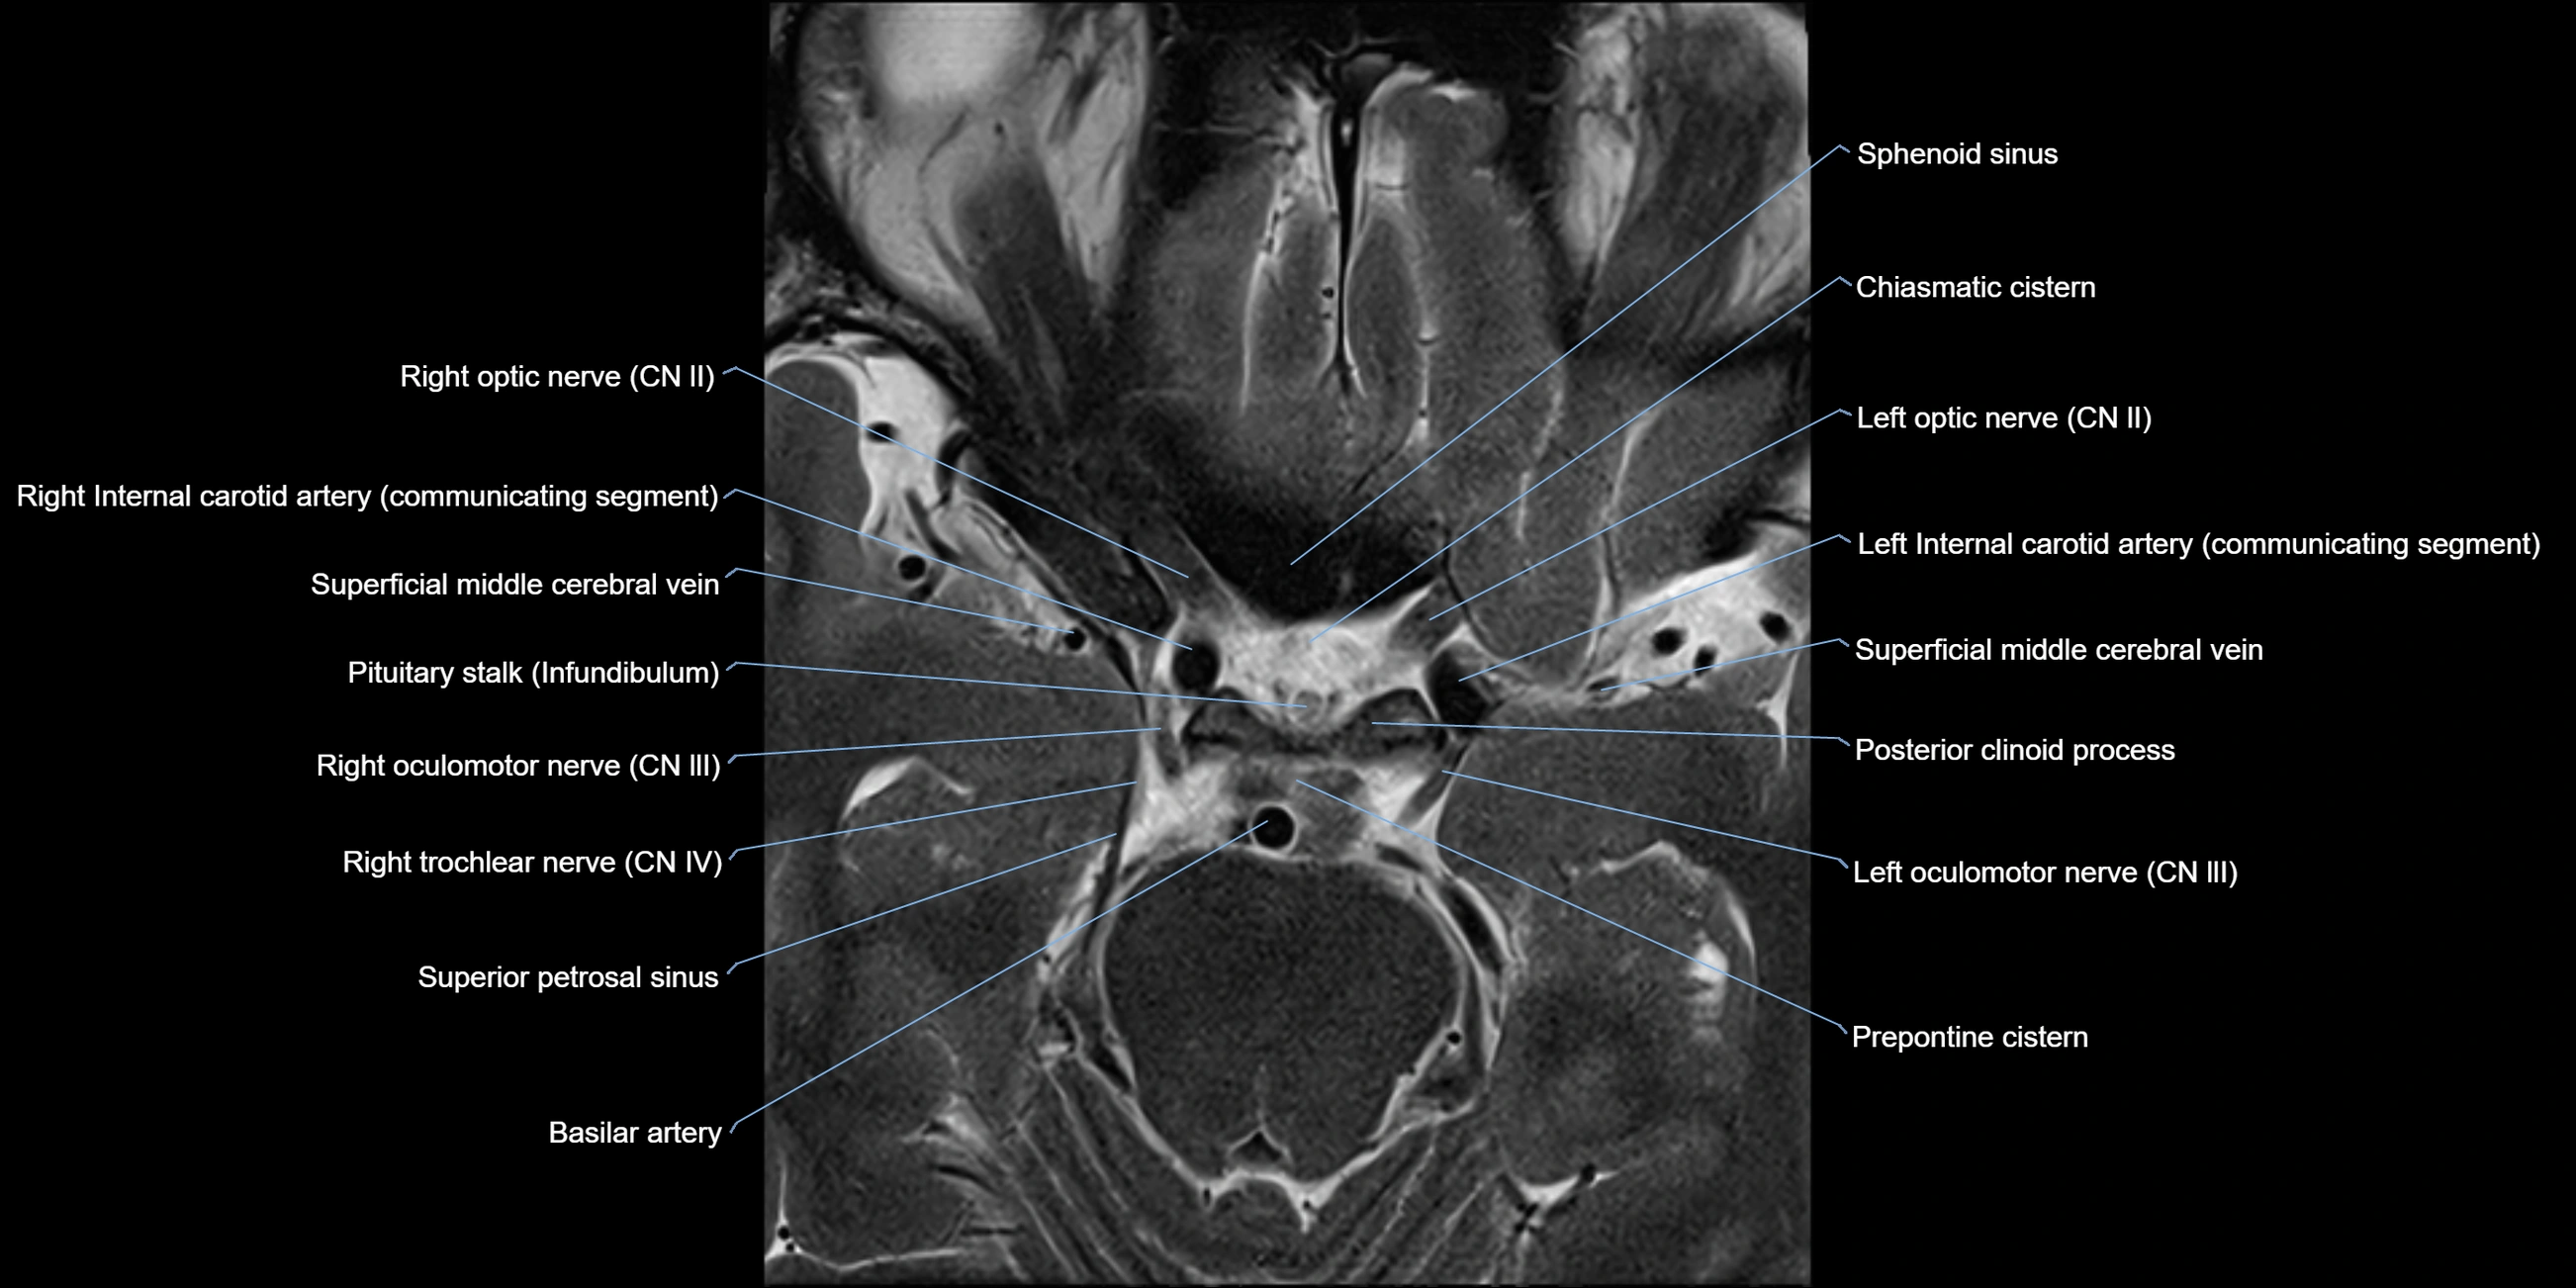

MRI Appearance

The abducens nerve is a small, thin, linear structure

Best visualized on high-resolution T2-weighted 3D MRI sequences (e.g., FIESTA or CISS)

Seen as a hypointense (dark) line running from the brainstem at the pontomedullary junction, traversing the prepontine cistern, and entering Dorello’s canal under the petrosphenoidal ligament, then into the cavernous sinus, and finally the orbit

May be challenging to visualize in standard MRI due to its small size

Pathology may be inferred by absence, displacement, or enhancement of the nerve

MRI images